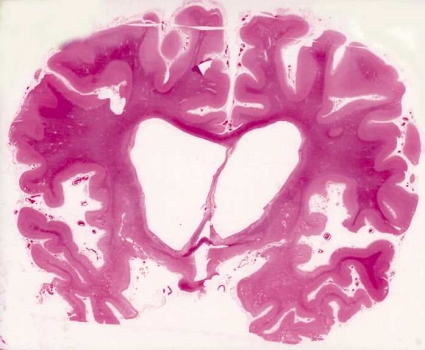

Vid FTD har hjärnan i många fall normal storlek och form trots en uttalad klinisk demensbild. I andra fall syns vidgade fåror mellan avsmalnade vindlingar frontalt, ibland även temporalt (Figur 1). Vaskulära skador är sällsynta.

Mikroskopiska fynd. Patologin vid FTD har paradoxalt nog som »karaktäristiskt« drag att vara relativt lindrig och ospecifik, vilket speglas i en diskret nervcellsuttunning i hjärnbarkens yttre tre lager (Figur 2). I vissa fall begränsas degenerationen till frontala områden (lateralt eller på undersidan, frontoorbitalt), i andra fall är den lindriga kortikala skadan utbredd inom stora delar av temporalloberna och når även parietallobernas främre delar. Framträdande är en degeneration inom det limbiska komplexet, speciellt främre cingulum [2, 32].